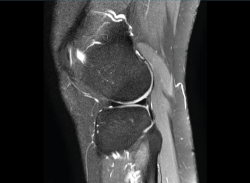

1.2.2. Ligamento cruzado anterior (LCA) (Figuras 40, 41, 42, 43 y 44)

Figura 40. Corte de secuencia sagital T2 Fat-Sat de resonancia magnética de rodilla: ligamento cruzado anterior normal.

Figura 41. Cortes de secuencia sagital T2 Fat-Sat de resonancia magnética de rodilla: rotura central del ligamento cruzado anterior.

Figura 42. Cortes de secuencia sagital T2 Fat-Sat: rotura proximal del ligamento cruzado anterior.